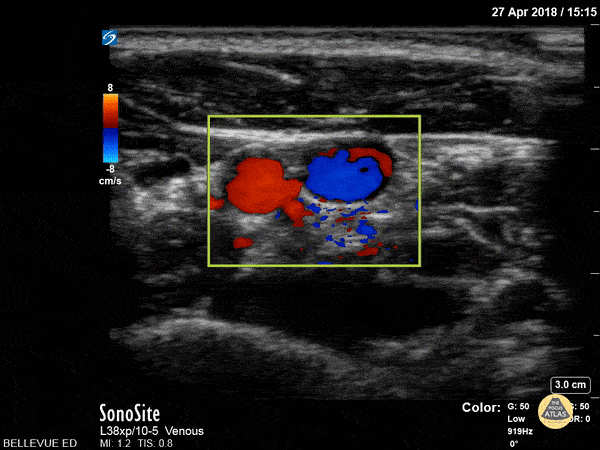

This clip shows the common carotid artery (red) and internal jugular vein (blue) in cross-section side by side using color doppler overlay. The sternocleidomastoid muscle is seen in cross-section at the top of the screen. Hannah Kopinksi and Dr. Lindsay Davis - NYU Emergency Medicine